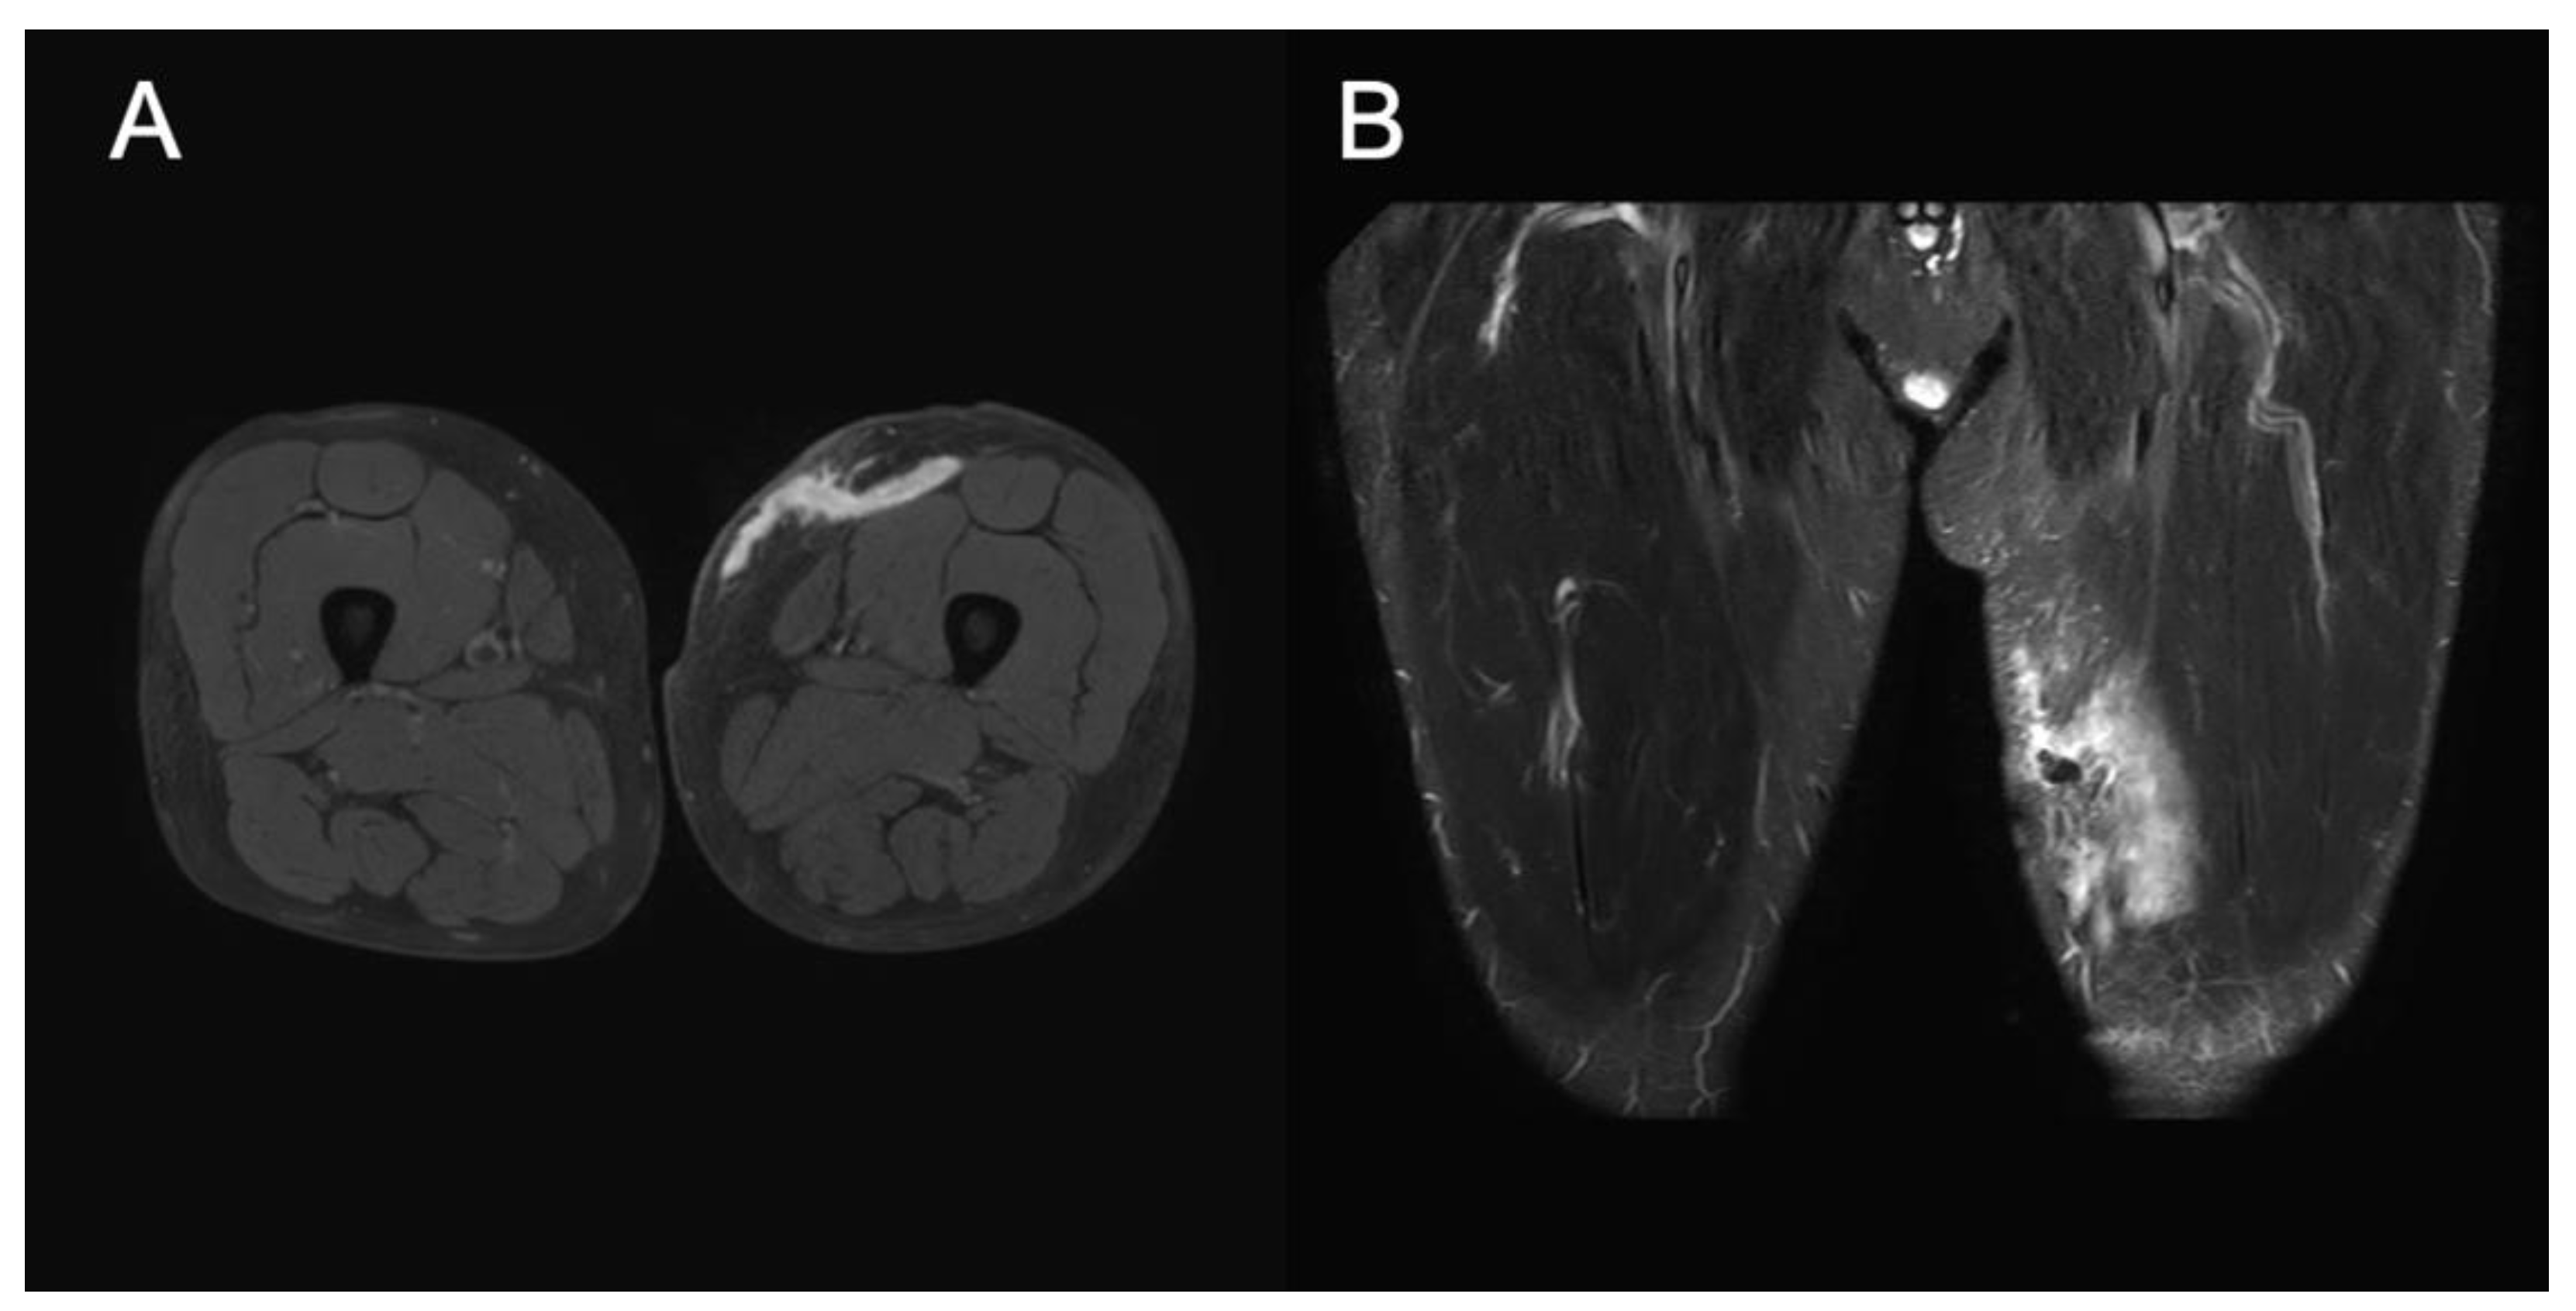

Figure 3. MRI on day 14 after discharge Axial T1 fat suppression MRI shows hyperintense hematoma between the subdermal fat and fascia (A). Coronal short tau inversion recovery MRI shows a longitudinal, hyperintense hematoma about 100 mm in length between subdermal fat and fascia (B). Hematoma was smaller than before because exudate and clots were extracted from two holes that had been necrotic plaques 2 days earlier in both Figure A and B.

A 52-year-old Japanese man was transported to our hospital for further workup of a left thigh injury. He had fallen from a motorcycle after colliding with a car at a speed of around 30 km/h. He was initially transferred to another hospital, where contrast-enhanced computed tomography (CT) showed left thigh hematoma with extravasation from the superficial femoral artery. The patient was referred to our hospital for interventional radiology (IVR). The patient had a medical history of adjustment disorder with anxiety and had been prescribed sertraline hydrochloride and hydroxyzine hydrochloride once daily and clotiazepam as needed when he felt anxious. His habitual activities and family history were unremarkable. He was a salesman living with his parents. On arrival in the emergency room, vital signs were: temperature, 36.6°C; heart rate, 66 beats/min with regular rhythm; respiratory rate, 20 breaths/min; blood pressure, 118/94 mmHg; and oxygen saturation, 97% on room air. Glasgow Coma Scale score on arrival was 15 (E4V5M6). On examination, the patient was alert and complained of left thigh pain. The trachea was central, with neither crackles nor decreased breath sounds heard on auscultation. The abdomen was not distended. Examination of cranial nerves showed no abnormalities. Bruising was seen around the left thigh (Figure 1A). Examination of the other limbs showed no abnormalities. Contrast-enhanced CT of the left thigh revealed hematoma with extravasation of a branch of the left superficial femoral artery, but no apparent aneurysms or fractures of the femur or pelvis (Figure 1B). IVR was therefore not indicated and observational management with compression bandages was applied. The patient was admitted to our hospital for pain management and discharged on hospital day 6. He left hospital able to walk unaided. The patient subsequently sought medical aid and visited our emergency department (ED) with left chest pain 2 days after discharge. He was advised to use acetaminophen for pain. Five days after discharge, he again visited our ED with the same left chest pain along with swelling in the left thigh and was again advised to use acetaminophen for pain. He revisited our ED 10 days after discharge complaining of pain, increased swelling, and loss of local sensation in the left thigh. CT of the thigh showed subcutaneous hematoma in the left thigh with no evidence of fracture (Figure 1C). Gross inspection 10 days after discharge revealed two necrotic plaques of roughly the same size with induration of the skin in surrounding areas (Figure 1D). Percutaneous aspiration was performed and 15 mL of bloody serosanguineous fluid was drained by needle aspiration (Figure 1E) along with a total of 100 mL of clots after rupture of the two necrotic plaques. Compression dressing was applied to the involved area using gauze and elastic bandages. A follow-up visit to another outpatient clinic was made 12 days after discharge, where wound care was provided. No necrotic tissue was observed, because follow-up treatment was provided relatively soon after the injury (Figure 2A). MRI of the left thigh was performed 14 days after discharge. T2-weighted MRI revealed cystic masses under the subcutaneous fat layer without a peripheral ring or capsule, and MLL was confirmed (Figure 3A,B). Considering that the patient was ambulant, we changed the treatment plan and applied a single-use disposable portable NPWT system (PICO system; Smith & Nephew, London, UK) after several weeks of compression treatment (Figure 2B,C). NPWT dressings were changed with simultaneous serial debridement at 3- to 4-day intervals for 57 days. MLL completely resolved, but the patient felt discomfort and skin indentation over the site of MLL (Figure 2D).